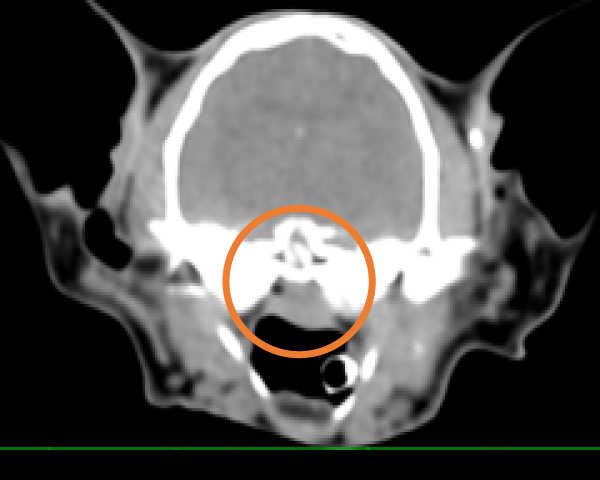

CT検査にて気管の圧迫を確認

内視鏡の位置をCアームで確認し正確に場所の把握が可能

2.8mmと5mmの内視鏡を用いて気管と食道両方の観察・生検が同時に実施可能